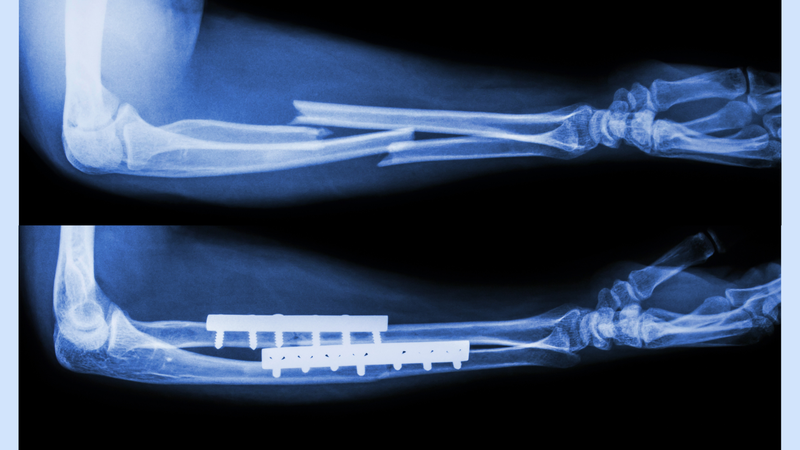

Các chấn thương thường cần chụp X-quang xương cẳng tay bao gồm: Gãy xương cẳng tay, trật khớp cẳng tay, viêm xương, viêm khớp, loãng xương, nhiễm trùng và các khối u xương lành tính hoặc ác tính. Đặc biệt, gãy hai xương cẳng tay là loại tổn thương cần thiết phải chụp X-quang xương cẳng tay ở tư thế thẳng và nghiêng.

Ngoài ra, chụp X-quang xương cẳng tay còn được tiến hành để kiểm tra tình trạng xương sau khi bó bột hoặc để đánh giá mức độ phục hồi của xương bị gãy hoặc rạn.

Tóm lại, chụp X-quang xương cẳng tay là một công cụ chẩn đoán hữu ích và phổ biến trong lâm sàng để đánh giá các tổn thương và bệnh lý của khu vực này. Kỹ thuật chụp X-quang ở các tư thế thẳng và nghiêng cho phép bác sĩ nhìn rõ hơn về cấu trúc xương và các mô liên quan, từ đó có thể chẩn đoán chính xác và có phương pháp điều trị phù hợp.